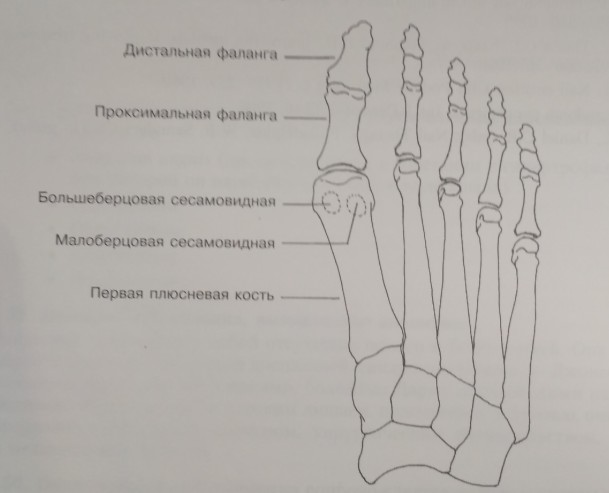

Перелом сесамовидной кости: Визуализация травмы и её лечение